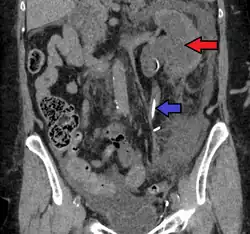

Urine jets[16]